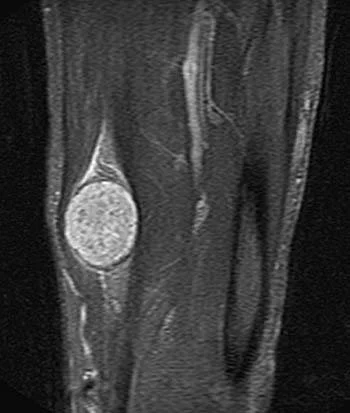

Τι δείχνει η MRI/MR νευρογραφία και ποια είναι τα χαρακτηριστικά ευρήματα;

Η MRI επιβεβαιώνει τη σχέση με το νεύρο, περιγράφει τα όρια/μέγεθος και βοηθά στον ασφαλή χειρουργικό σχεδιασμό.

Η MRI με σκιαγραφικό (ή MR νευρογραφία) είναι η εξέταση εκλογής για όγκους περιφερικών νεύρων. Τυπικά χαρακτηριστικά σβαννώματος περιλαμβάνουν:

- Καλά περιγεγραμμένη ατρακτοειδής βλάβη που σχετίζεται με το νεύρο.

- Ενίσχυση με γαδολίνιο.

- Ευρήματα όπως το σημείο «στόχου» σε ορισμένες περιπτώσεις (target sign).

- Δομική συνέχεια του νεύρου.

Η MRI δεν βοηθά μόνο στη διάγνωση αλλά καθορίζει τη σχέση του όγκου με τις παρακείμενες δεσμίδες, δομές, αγγεία και καθοδηγεί τη στρατηγικό σχεδιασμό του χειρουργείου.